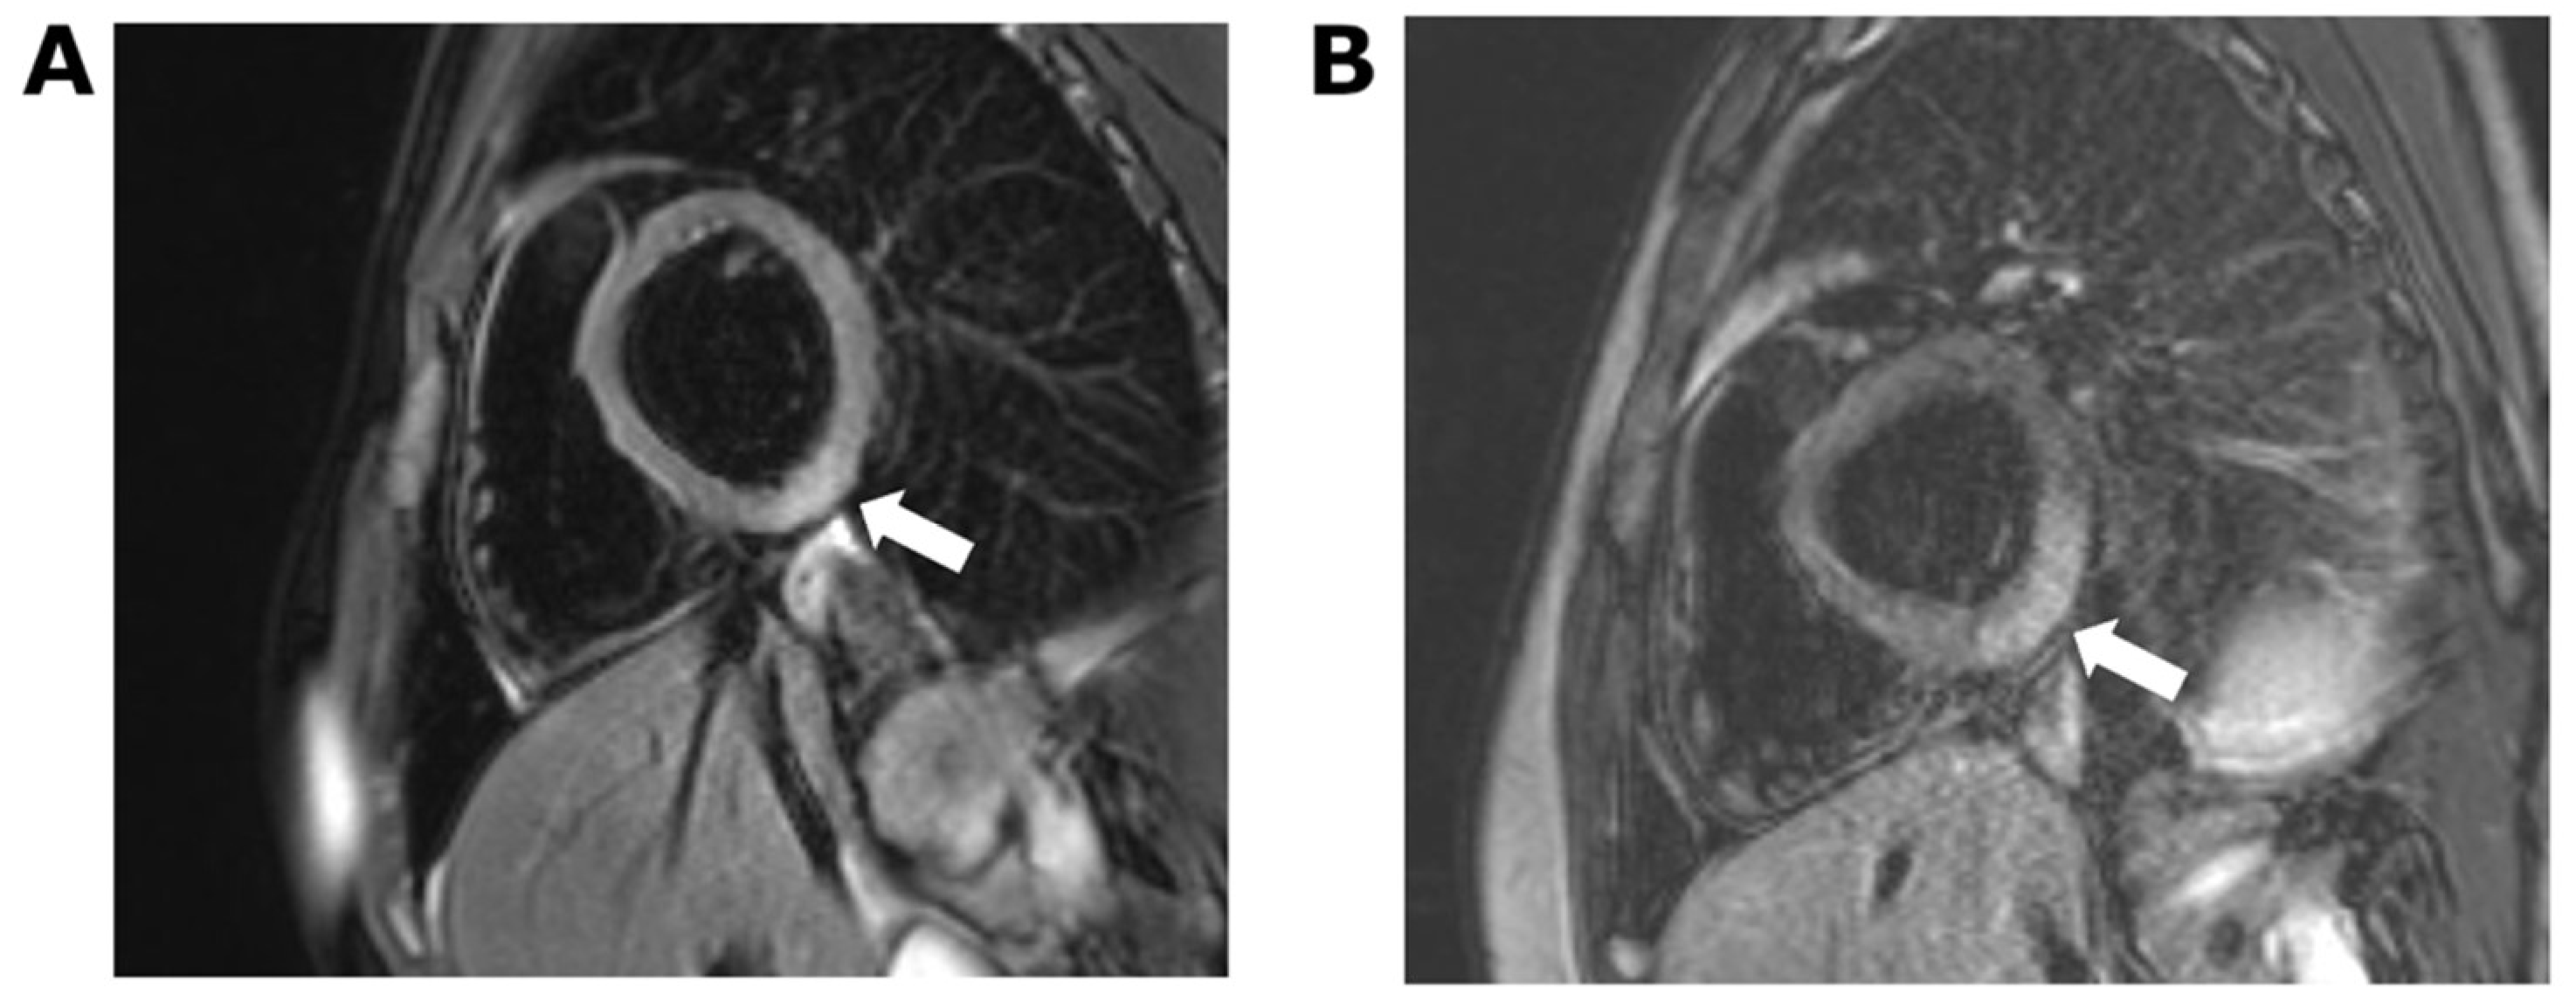

2. Case 1

3. Case 2